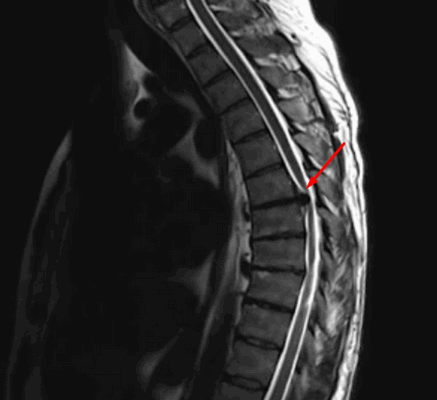

МРТ головного мозга выявляет скопление гемосидерина. Наиболее чувствительны градиентные Т2-взвешенные МРТ. Часто отмечается атрофия червя мозжечка, особенно, видимая хорошо на сагиттальных Т1-взвешенных МРТ.

МРТ головного мозга. Т2-взвешенная аксиальная МРТ через ствол. Тонкое темное кольцо гемосидерина вокруг ствола и в мозжечке. Сидероз головного мозга.